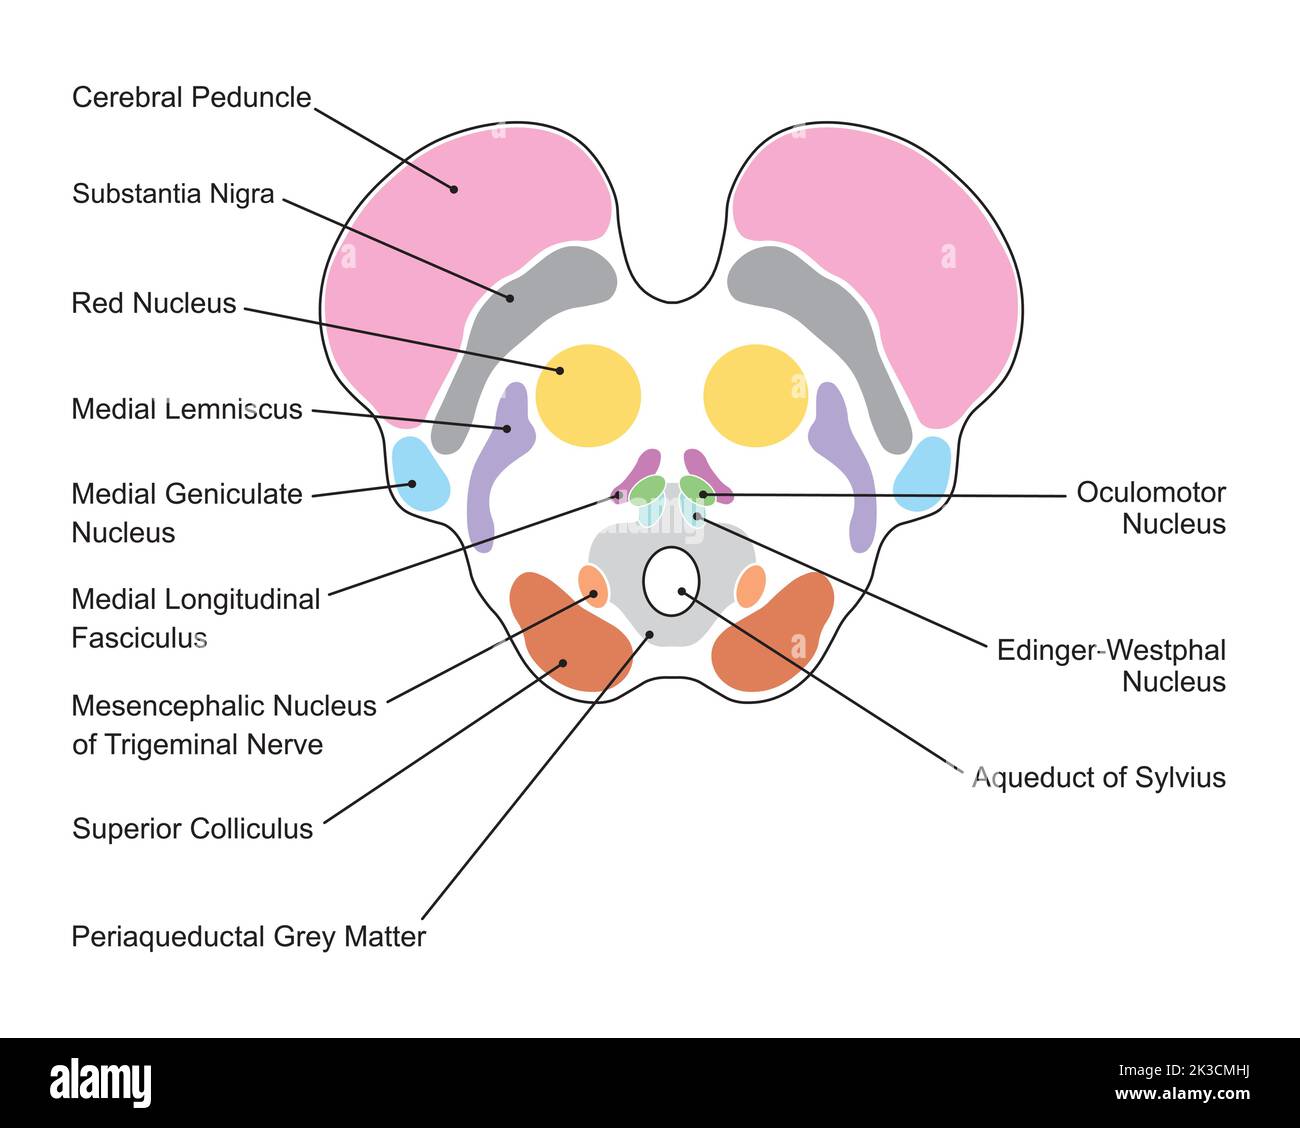

RF2K3CMNG–Wissenschaftliche Gestaltung der Anatomie des Mittelhirns. Axialer Schnitt auf der Ebene des Oberen Kollikulus. Bunte Symbole. Vektorgrafik.

RF2K3CMHJ–Wissenschaftliche Gestaltung der Anatomie des Mittelhirns. Axialer Schnitt auf der Ebene des Oberen Kollikulus. Bunte Symbole. Vektorgrafik.

RF2K3CMH3–Wissenschaftliche Gestaltung der Anatomie des Mittelhirns. Axialer Schnitt auf der Ebene des Oberen Kollikulus. Bunte Symbole. Vektorgrafik.

RM2AXFEW1–Ein Handbuch der Anatomie. ide. Itrests auf dem mittleren Längsfasciculus und liegt nahe an der Mittellinie. Die aus diesen Zellen entstehenden Axone gehen nach unten (cau- DER OCULOMOTOR-NERV 447 dally) und seitlich entlang des Randes des Aquäduktgraues, dem sie bis zur Mittellinie folgen; hier decussieren die Nerven am oberen Rand des übergeordneten medullären Velums und treten an der medialen Grenzlinie der Brachia contiva auf. Sie sind die kleinsten der Großhirnnerven. Diese Kerne erhalten Fasern aus dem motorischen Bereich der gegenüberliegenden Gehirnrinde durch die Pyramide. Fasern des medianlongitudinalen Fasciculus a

RM2AWGFW4–Erkrankungen des Nervensystems .. . "Ortion", die wir als mittleren Regen bezeichnen; hier auch wir. Abb. 43.-Rase der Gehirnnerven von Braix axd. Suchen Sie nach den Hauptabteilungen des Menschen, der Korpora qtiadrigemina (siehe Abb. 44und 45) oben, die Fissure des Sylvius unten und darunter die Faser, die an den oberen Stiegenkeln des Kleinhirns und des Pedunculi-Kleinhirns massiert wird (Abb. 46, 47, 48, 49). Seine Nticlei (Neuronzellen) liegt auf der gesamten Länge des Bodenbelägen des Aquädukts von Sylvius, von seinem frontalen Ursprung fast bis zu seinem kaudalen Ende;5 52 HISTOLOGIE DES ZENTRALEN NERVENSYSTEMS die Kerne des

RM2AWH0CG–Erkrankungen des Nervensystems .. . Abb. 13.-Diagramm des Gehirns, Der Pedonkel. (Nach Obersteiner.) Qa, Anterior corpora quaderigemina; AS, Aquädukt von Sylvius; FU:, pos-terior longitudinal Bundle; Tg, teg-mentum; Nt, roter Zellkern; SnS, substantia nigra soemmeringi; 1, frontalpontal Trakt; 2, Trakt des Motors. Kraniale Nerven; S, Hirngewebe, Hirngewebe, Hirngewebe, Hirngewebe, Hirngewebe, 5. 6, Bündel vom lem-niscus zum Fuß; 7, Stratum intermediimi. Die makroskopische ANATOMIE DES ZENTRALEN NERVENSYSTEMS 21 Rior Eminence im Menschen ist excleclingiy klein c

RM2CE564C–. Erkrankungen des Nervensystems . Abb. 43. – Basis der Braix axd Hirnnerven. Sucht nach ihren Hauptabteilungen im Menschen, der Korpora quadrigemina (siehe Abb. 44und 45) oben die Spalte von Sylvius unten, und darunter die Fasermasse der oberen Pedunkles des Kleinhirns und der Pedunculi cerebri (Abb. 46, 47, 48, 49). Seine Kerne (Neuronenzellen) liegen entlang der gesamten Länge des Aquädukts von Sylvius, von seinem frontalen Ursprung fast bis zu seinem kaudalen Ende;5 52 HISTOLOGIE DES ZENTRALNERVENSYSTEMS die Kerne der trochlearen Nerven liegen posteriorly dort, wo der aque-Ductus liegt

RM2CHEGP9–. Das Nervensystem: Ein elementares Handbuch der Anatomie und Physiologie des Nervensystems für den Einsatz von Studenten der Psychologie und Neurologie. Diese Nut der dritten Hirnnerven entstehen. Wo die Krura an die Ponen anschließt, liegen sie nahe beieinander, aber wenn sie vorwärts gehen, divergieren sie, so dass ein dreieckiger interpedukulärer Raum. Innere Struktur. - in einem transversem Abschnitt über die Mitte des Gehirns kann das Aquädukt von Sylvius in der Nähe der überlegenen Oberfläche (Abb. L 56, S. Graue Materie. - die wichtigen Massen der grauen Materie dieser Region vielleicht in vier Gruppen angeordnet : (1) die graue Materie surroun